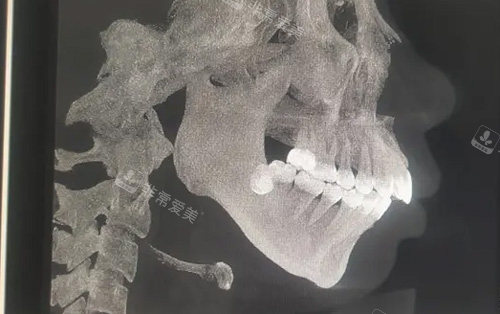

需要做正颌手术的骨骼图